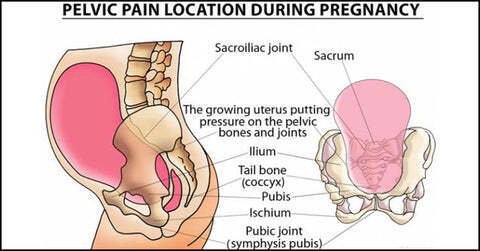

② 骨盤制御が崩れる

側弯がある人の多くに見られるのが

-

片脚重心

-

片側殿筋の機能低下

-

腹圧の抜け

つまり

腰で支えるしかない状態になります。

③ 神経が“引っ張られる”

側弯そのものよりも問題なのは

神経の通り道が歪むこと。

神経は圧迫だけでなく

牽引ストレス(引っ張り)にも弱い。

ここが見落とされがちです。